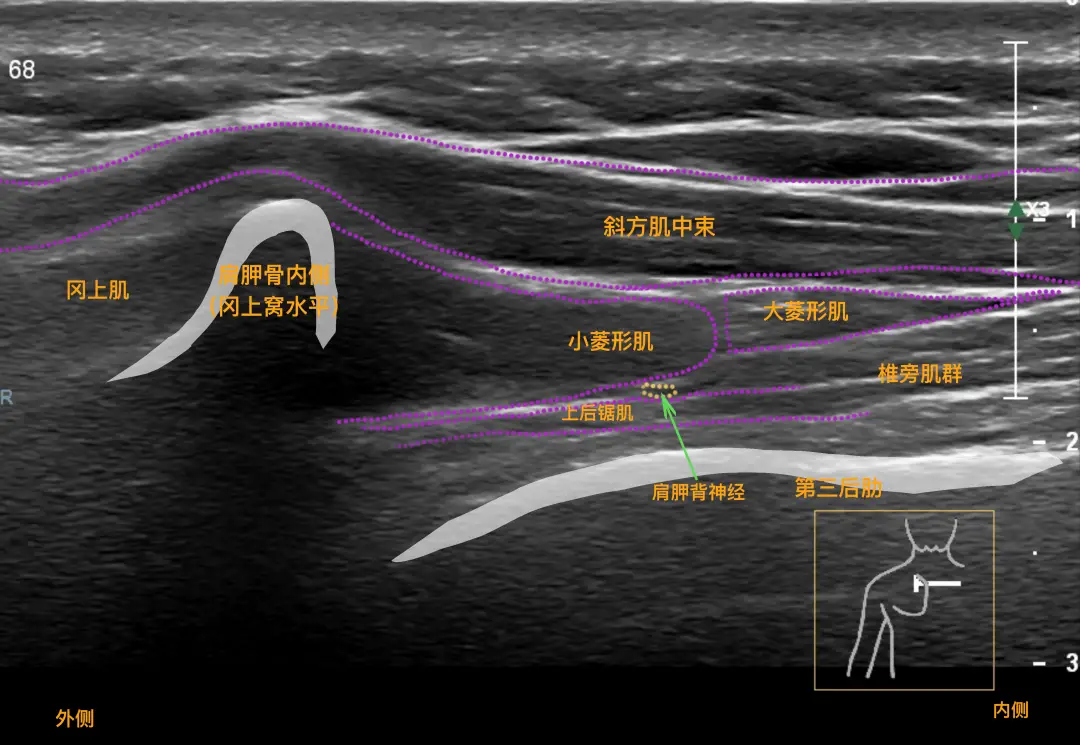

一、超声穿刺介入 超声穿刺介入技术是一种结合高分辨率超声与介入治疗的先进方法。在肌骨超声的引导下,医生能够清晰、实时地观察到穿刺针的针尖,确保穿刺路线准确,直达病变位置,进行精准给药或治疗性操作。 超声穿刺介入技术的优势包括: 精确诊断、精准治疗:药物直达病灶,有效缓解疼痛,同时避免损伤邻近重要结构,如血管、神经和脏器。 恢复运动功能:点对点治疗,有效缓解各种关节、软组织和神经疾病引起的急性或慢性疼痛,改善和恢复关节的运动功能。 微创治疗:减少开放性手术的需要,提高治疗安全性。 二、肌骨超声的功能 肌骨超声主要应用高频超声来诊断肌肉骨骼系统疾病,具有以下功能: 清晰显示:能够清晰显示关节、肌肉、肌腱、韧带、周围神经等浅表组织结构及其发生的微病变,如炎症、外伤、肿瘤等。 评估功能状态:确定病变的范围、类型和程度,评价肌腱和韧带的功能状态,评估临床治疗疗效。

三、肌骨超声的临床检查范围 肌骨超声的临床应用范围广泛,包括但不限于以下几个方面: 肌肉病变:肌肉损伤、骨化性肌炎、肌疝、儿童肌性斜颈等。 肌腱病变:肩袖病变、网球肘、高尔夫球肘、跟腱病、足底跖腱膜炎以及肌腱旁滑囊积液等。 韧带病变:脚扭伤后踝关节外侧距腓前韧带损伤、跟腓韧带损伤,踝关节内侧三角韧带损坏,膝关节内、外侧副韧带病变等。 骨与软骨病:婴儿髋关节发育不良的筛查,肋骨骨折,部分骨肿瘤等。 关节病变:检测类风湿关节炎滑膜炎、肌腱腱鞘炎、骨侵蚀、银屑病关节炎以及痛风性关节炎等。 神经病变:神经卡压症、神经脱位、神经肿瘤、解剖变异和创伤等。 总的来说,肌骨超声作为一种先进的影像检查技术,在肌肉骨骼系统疾病的诊断、治疗及疗效评估中发挥着越来越重要的作用。 即刻关注凯信微信号xzkxele,就能查看更多关于彩超机、B超机、笔记本彩超机、眼科AB超的详情。(只需在公众号里搜“凯信超声”或扫描下方的二维码就可以加关注! 如需咨询报价信息,可联系客服热线15050003098 400-928-6626. |